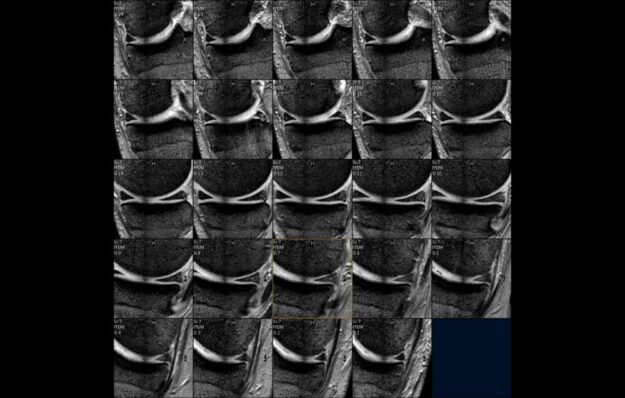

RM Avampiede

La struttura del piede, a causa dei suoi assi sempre variabili e discontinui) non consente la creazione di un protocollo standard per uno studio generale di tutto il piede. E’ quindi necessario dividere il piede in 4 zone principali: dita, metatarsi, tarso, caviglia; ciascuno con i suoi piani e protocolli specifici. STUDIO DEI METATARSI QUESTIONARIO…